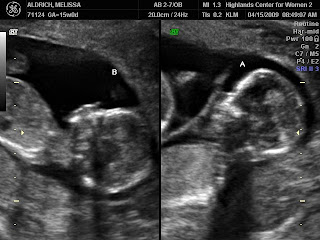

to looking like sweet babies!

The miracles of God knitting little ones in my womb is just incredible to watch by ultrasound!

Do you think they’ll be identical or not based on these photos?